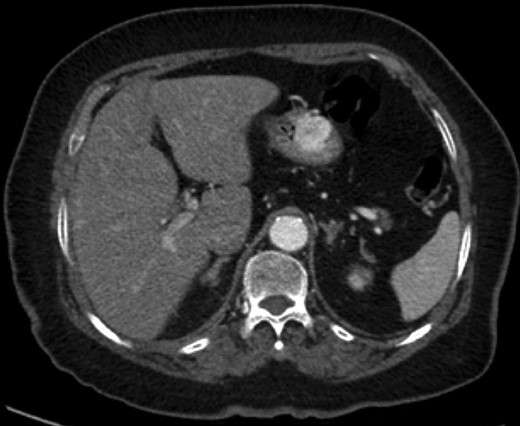

A 70–year-old male presented with light headedness, shortness of breath and 2 days of bright red blood per rectum progressing to melena. His hemoglobin was 92 g/l, a decrease from 144 g/l 10 days prior. Upper endoscopy demonstrated a 3-mm polyp in the duodenal cap (biopsy would be reported as a completely excised carcinoid tumor). Colonoscopy demonstrated a bleeding, edematous region in the ascending colon. Biopsy was non-diagnostic. CT demonstrated a 2.3 × 1.6 cm ascending colon lesion with hyperenhancement in the arterial phase and persistent enhancement in the portal venous and delayed phases. On octreotide scan, the lesion had intense uptake, consistent with a carcinoid. The clinical picture was in keeping with two synchronous primary carcinoid tumors. Laparoscopic converted to open right hemicolectomy was performed without complication. Final pathology demonstrated a GT with negative margins, 26 negative lymph nodes, 1 mitosis per 50 hpf, no vascular invasion and absence of necrosis. Follow-up for the colonic GT will include a colonoscopy and abdominal CT 1 year following surgery, as well as chromogranin A level every 6 months. Chromogranin A was mildly elevated preoperatively. For his duodenum, he will be followed with Esophagogastroduodenoscopy +/− endoscopic ultrasound (EUS) every 3–6 months initially.

Endoscopic findings of gastric GTs are that of a submucosal mass, typically in the antrum or distal body, with either normal mucosa or ulceration [3, 4] (Fig. 1). CT shows a well-defined submucosal tumor with a clear margin, strong enhancement in the arterial phase, and prolonged enhancement in the delayed phase [4, 5] (Fig. 2). Often confused with GIST, the distinguishing features are that the density of GISTs is lower than that of GTs, and GISTs do not exhibit prolonged enhancement in the delayed phase [5]. On EUS, the GT is found in the fourth endosonographic layer, with a heterogeneous appearance. In one small study of seven gastric GTs, six demonstrated the characteristic ‘peripheral halo’ sign around the tumor [5].